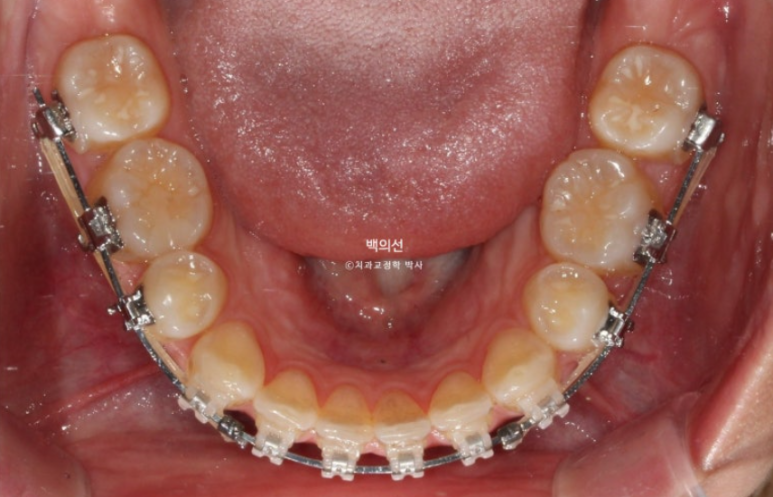

치료기간이 이미 2년 10개월이 된만큼 교정치료 마무리 단계입니다.

그런데 엑스레이상 치아 뿌리의 평행이 맞지 않는 부분들이 보입니다.

뿌리가 맞닿아 있으면 발치공간이 잘 닫히지 않을뿐더러 여러모로 좋지 않습니다.

치아 뿌리는 안 보이는 부분이지만 평행하게 맞추는 것이 장기적으로 환자분께 좋습니다.

아직 맞지 않는 중심선은 남은 공간이 닫히면 자연스레 맞아질 것 입니다.